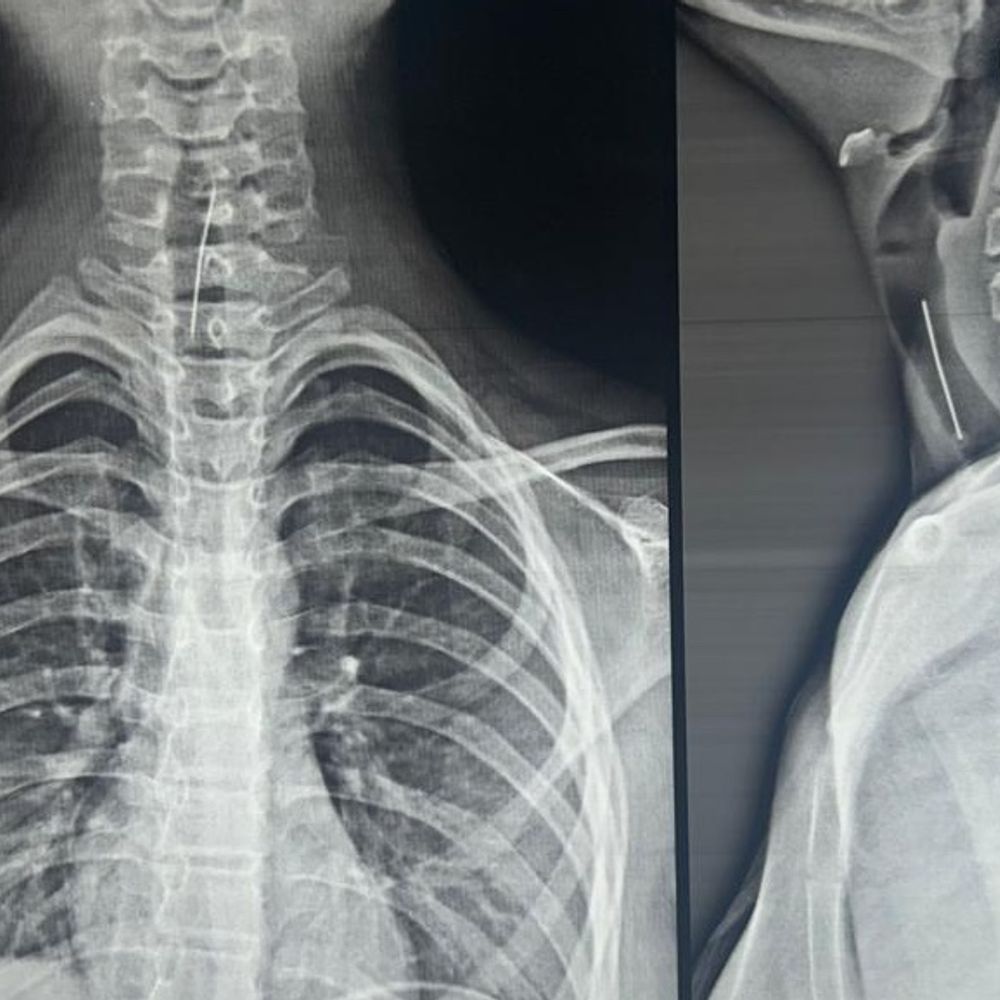

વાલીઓ માટે લાલબત્તી સમાન કિસ્સો:ભરૂચની 13 વર્ષીય બાળકીની શ્વાસનળીમાંથી 4 સેમીની પિન સર્જરી કરી બહાર કાઢી